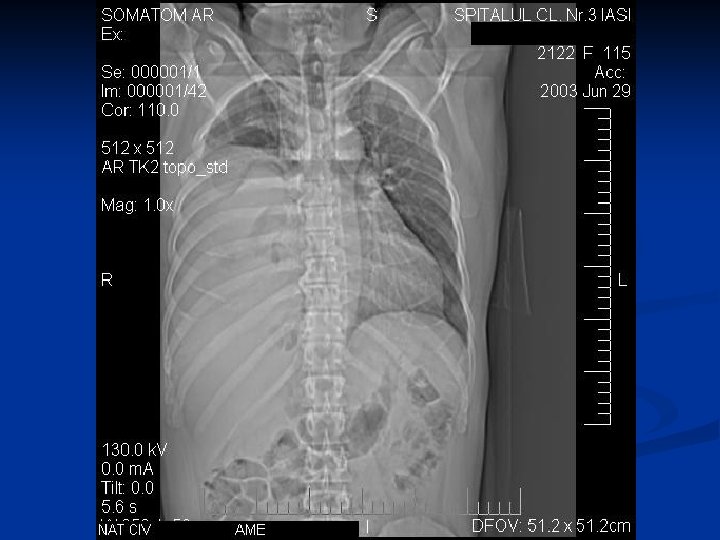

Caracteristici generale n n n Boala parazitara determinata de Taenia echinococcus granulosus. Descrisa inca de pe vremea lui Hipocrat si a lui Galen. Termenul de “chist hidatic” utilizat de Rudolphi in 1908. Localizarea pulmonara este a doua ca frecventa dupa cea hepatica. Boala cu distributie endemica in regiunea mediteraneana, Orientul Mijlociu, Australia, Noua Zeelanda, America de Sud.

Asociere CHP cu CHH

Metode de diagnosticare